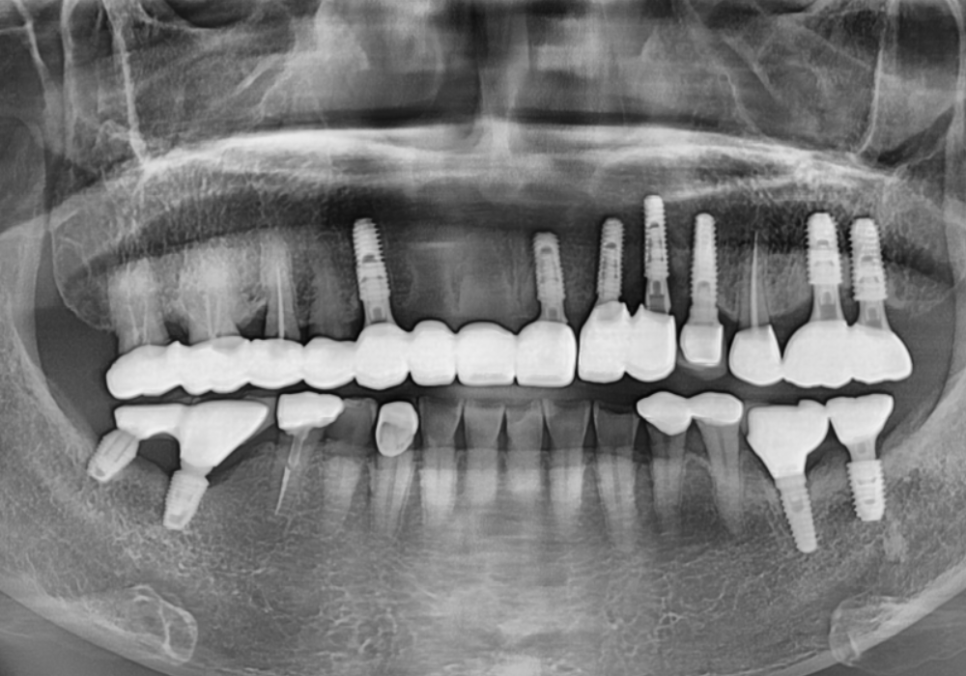

CT 상으로 확인한 오른쪽 위 송곳니(#13)는

뿌리 끝 염증으로 잇몸뼈까지 녹아있었죠.

치료 계획

앞니 브릿지 탈락

결국 깊은 고민 끝에

상해버린 치아 4개를 발치하고,

임플란트 치료를 진행하기로 결정했습니다.

이때 저는 환자분의 심리적인 부담과

비용적인 고민을 조금이라도 덜어드리기 위해,

251023

앞니 4개를 발치하더라도

임플란트는 단 2대만 식립하는 계획을

제안해 드렸어요.

다행히 다른 곳은 뼈 상태가 양호해,

염증으로 뼈가 녹았던 송곳니 부위에만

꼭 필요한 만큼의 뼈이식을 병행하기로 했습니다.

치료 결과, 완성된 임플란트

앞니 브릿지 탈락, 씌워둔 게 빠졌어요. 다시 붙일 수 있을까요?

임플란트 식립 2개월 뒤,

뼈와 완벽히 굳은 것을 확인하고

지르코니아 보철로 마무리를 해드렸습니다.

260106

251020 (전) 260106 (후)

주변 치아와 구분되지 않을 만큼

자연스러운 색상과 배열로

완성된 모습을 보시고

환자분께서도 매우 만족해하셨습니다. ^^